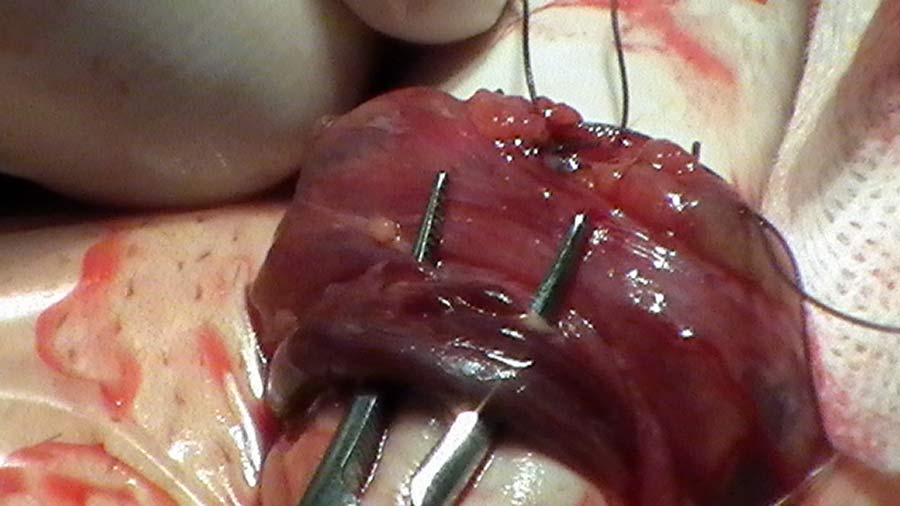

• mikrochirurgická varikokélektomie – je považována za nejméně zatěžující operační léčbu s minimálním výskytem recidiv (0,6 - 2 %). Je minimálně invazivní i ve srovnání s výkony invazivní radiologie. Základní varianta mikrochirurgické operace varikokély využívá k diferenciaci (rozlišení), k selekci cév a dalších struktur semenného provazce pouze optické zvětšení v jednorovinném zobrazení (2D). Pokročilé technologie (Advanced Technologies) umožňují výrazně lepší diferenciaci a selekci operovaných cév a tkání prostorovým (3D) optickým zvětšením a s variabilním optoelektronickým zvětšením operační kamerou s projekcí obrazu na stěnu operačního sálu během operace. K hodnocení průtoku cévami semenného provazce užívají tyto technologie mikrovaskulární kontaktní Dopplerovskou diagnostiku umožňující spolehlivé zachování tepenné výživy tkáně varlat a zachování lymfatických cév. Takto prováděné operace je možné provést optimálně po stránce technické a co nejšetrněji pro pacienta. Mají menší rizika komplikací a lepší výsledky; tento způsob provedení operace je nazýván také High Performance Surgery.

Provádíme mikrochirurgické operace varikokél, vycházející z postupu prof. Marka Goldsteina, Department of Urology, Weill Cornell Medical College, New York.

Využíváme možností Advanced Technology, navazující na předoperační 3D Dopplerovskou vysokofrekvenční ultrasonografii s 3D Color Flow Mapping Dopplerovským zobrazením spermatických cév. Během operace používáme mikrovaskulární Dopplerovskou diagnostiku. Operace provádíme v šetrné celkové anestezii, při jednodenní hospitalizaci.

Jde o nejmodernější mikrochirurgickou cévní operační technologii, kdy s pomocí mikrovaskulární Dopplerovské sondy o šíři 1 mm a frekvenci 16 MHz hodnotíme během operace proudění jednotlivými cévami semenného provazce. Cévy jsou sledovány prostorovou optickou soustavou 3D EyeMag, umístěnou na hlavě operatéra, a současně jsou zobrazeny operační kamerou s variabilním optoelektronickým zvětšením. Obraz je promítán dataprojektorem na stěnu operačního sálu; tato kombinace zajišťuje operatérovi i jeho asistentům optimální přehled. Technika operace byla vypracována v USA, odkud také pochází veškerý materiál, který je použit k uzávěru postižených cév a k rekonstrukci vrstev operační rány. Plně vstřebatelný materiál, používaný k rekonstrukci přístupové cesty (vlákna Vicrylu), se v předem stanovené době kompletně vstřebá, když už tkáň pacienta nepotřebuje jeho oporu.

Předoperační diagnostika - 3D Dopplerovská vysokofrekvenční ultrasonografie s 3D Color Flow Mapping Dopplerovským zobrazením spermatických cév poskytuje topografickou informaci o prostorovém rozložení struktur v oblasti, kterou budeme operovat (obr. 38 – 40). Podle nálezu plánujeme operaci. Operaci provádíme ze subinguinálního přístupu, kaudálně od anulus inguinalis externus. Neotevíráme přední stěnu inguinálního kanálu. Používáme stereoskopický 3D mikrochirurgický systém EyEMag a optoelektronický řetězec s operační kamerou s  variabilním zvětšením operačního pole – dříve na velkoplošné obrazovce (obr. 41,42), nyní s dataprojekcí na stěnu operačního sálu. Po uvolnění spermatického provazce tento anteponujeme před ránu a podkládáme měkkými plastovými hadičkami (obr. 43). Pečlivě revidujeme, zda nejsou přítomny extrafunikulárně probíhající venózní kolaterály; pokud je nalezneme, provádíme jejich ligaturu (obr. 44). Otevíráme zevní spermatickou fascii, za pomoci mikrovaskulární Dopplerovské sondy 16 MHz o šíři shodné s šíří arterie = 1 mm (obr. 45, 46) identifikujeme, preparujeme a prezervujeme spermatickou arterii. Ta má nejčastěji dvě hlavní větve - jednu povrchní, jednu hlubší (obr. 47). Izolaci od těsně naléhajících venózních větví je nutno věnovat dostatek času a opatrnosti, protržení stěny žilní vede k hemoragii a zhoršení přehledu v zorném poli. Manipulace s cévami při preparaci vede ke kontrakci jejich svaloviny, ke snížení perfuze a intenzity arteriálního Dopplerovského signálu. Aplikací muskulotropního spasmolytika (Buscopan) na stěnu cévní tuto kontrakci eliminujeme. Při ligaturách na arterii naléhajících vén kontrolujeme, zda dotažení ligatur nesnižuje průtok krve arterií (obr. 48). Ligatury provádíme materiálem firmy Ethicon – Johnson and Johnson o šíři 3/0 – 4/0. Dopplerovský záznam sledujeme ve formě akustické a grafické na obrazovce systému EzDop (obr.49). Vény, které nenaléhají na arterie, samostatně selektivně ligujeme (obr. 50, 51). Jako drenážní vény ponecháváme žíly provázející vas deferens, během operace hodnotíme stěnu těchto žil a jejich šíři. Dle předoperačního Dopplerovského vyšetření a peroperačního nálezu hodnotíme jejich funkční stav. Během preparace krevních cév prezervujeme pečlivě lymfatické cévy (obr. 52). Po kontrole kompletnosti výkonu a pečlivé hemostáze provádíme závěrečnou Dopplerovskou kontrolu zachování průtoku spermatickými arteriemi. Operujeme mikrochirurgickým instrumentáriem (obr. 53). Suturu zevní spermatické fascie provádíme atraumatickým Vicrylem 4/0, steh rány po vrstvách Vicrylem Plus 4/0, Vicrylem 3/0 a Vicrylem 3-4/0 Rapid (kůže). Incize kůže je délky asi 40 mm, podle vrstvy podkožního tuku (obr. 54). Výkon provádíme v cloně perorálním doxycyklinem 100 – 200 mg/ 1x 24 hodin, prevenci tromboembolické nemoci nízkomolekulárním heparinem.